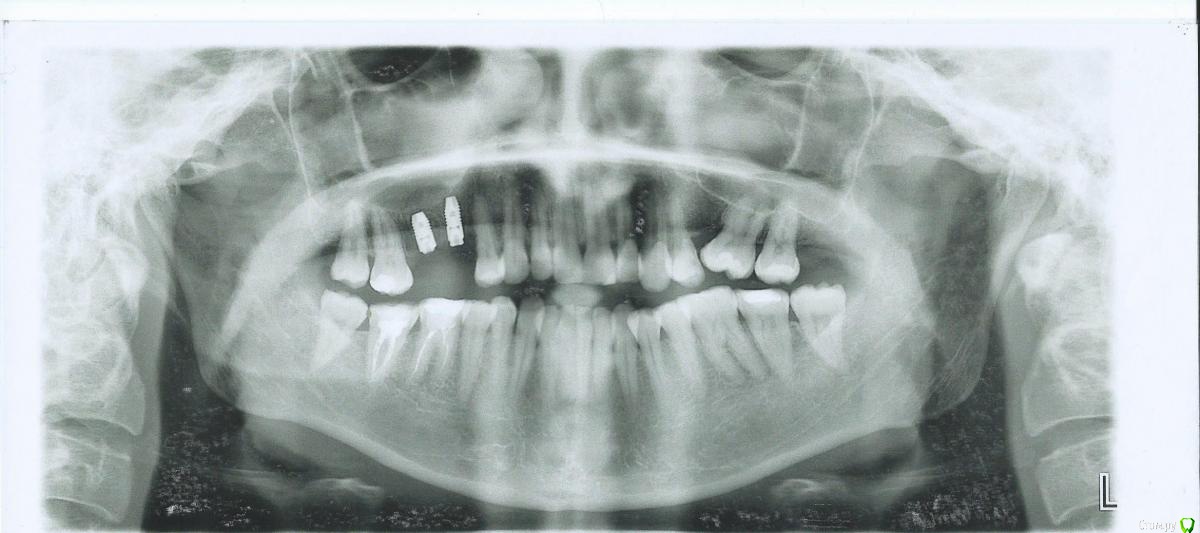

Allegro23 Опубликовано 19 ноября, 2016 Поделиться Опубликовано 19 ноября, 2016 (изменено) Добрый день. Есть ли, на ваш взгляд, признаки парадонтита? И какое бы порекомендовали решение? После удаления двух зубов этим летом стали бесопокоить дёсны - жжение, опухание, дискомфорт. Особенно опухает десна возле верхнего второго зуба на левой стороне челюсти и возле наклонившейся нижней шестёрки на той же стороне (там заменили прикорневую пломбу, десна немного опустилась от старой, распухание не проходит 2 месяца после замены пломбы). Лечат от гингивита, но дёсны по-прежнему беспокоят.Заранее благодарна всем за рекомендации. Изменено 19 ноября, 2016 пользователем Allegro23 Ссылка на комментарий

DmitrySH Опубликовано 19 ноября, 2016 Поделиться Опубликовано 19 ноября, 2016 Визуально надо смотреть. Я бы на консультацию к ортодонту отправил. Ссылка на комментарий

Allegro23 Опубликовано 19 ноября, 2016 Автор Поделиться Опубликовано 19 ноября, 2016 Визуально надо смотреть. Я бы на консультацию к ортодонту отправил. Есть ли какие-то другие очевидные проблемы, на ваш взгляд? Ссылка на комментарий